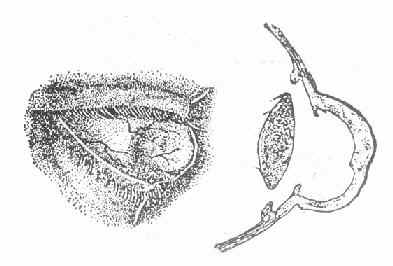

3.虹膜脱出(irisprolapse)角膜溃疡穿孔时,由于房水流出,虹膜可脱出于穿孔处,瞳孔失去圆形,呈瓜子状,其尖端朝向虹膜脱出处,(图6-3)此时眼压降低,眼球变软。在愈合过程中,可出现以下几种情况。

图6-3 虹膜局部脱出的正面与侧面示意图

(1)粘连性角膜白斑(adherentcorneal leucoma )虹膜脱出后,在虹膜表面上很快产生纤维蛋白性渗出物,凝聚在穿孔处及脱出的虹膜上,并将溃疡边缘与虹膜脱出部分固定起来,不使前房与外界相通,前房逐渐恢复。溃疡愈合后,在角膜瘢痕组织中,夹杂有脱出的虹膜组织。这种角膜瘢痕叫粘连性角膜白斑。(图6-4)

图6-4 粘连性角膜白斑